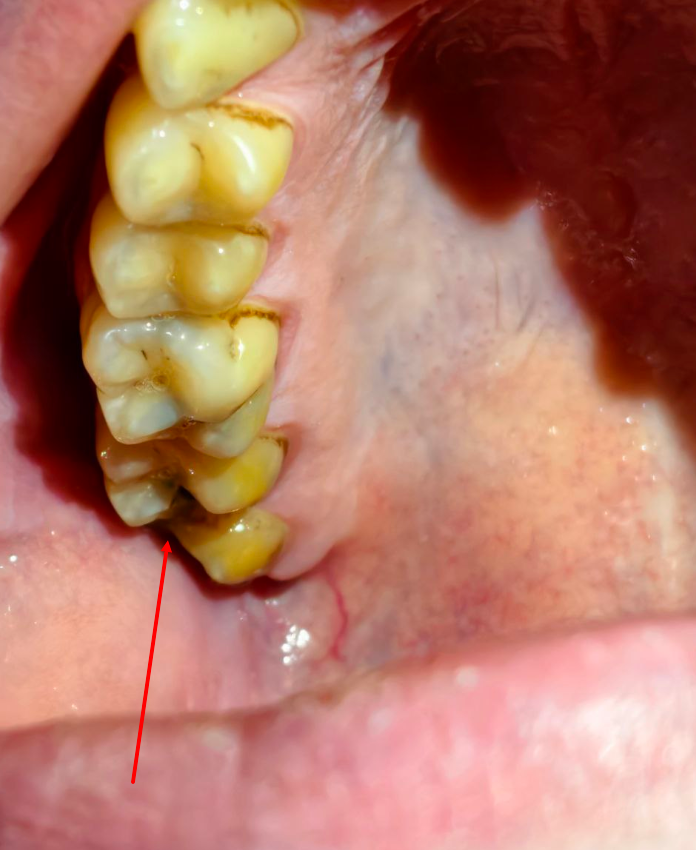

image.png

Аноны, которые лечили, удаляли зубы по ОМС или в частной клинике.

Расскажите почему и в чем был выбор и главный вопрос, сколько денег вы потратили?

У меня 3 дня назад сильно болел зуб снизу и сверху, оба дырявые (который на пикриле 13 назад стояла пломба, 11 лет назад выпала)

сейчас ощущение что они мягкие (правой частью рта не жую)

сейчас боль по меньше, думаю периодонтит, ну и кариес. Сколько в частной клинике выйдет лечение такой хуйни? плюс если коронки ставить.